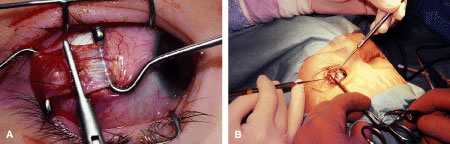

RECESSION PROCEDURE: FORNIX INCISION

This procedure is recession of the right medial rectus muscle. The eyelids are separated with a Barraquer open-blade wire eyelid speculum (Fig. 8). The open-blade design provides more room for exposure and makes it easier to pass the suture needles, especially in small children or when large recessions are performed. The globe is grasped with a Lester forceps at the limbus. It is best to grasp the limbus with the forceps held perpendicular to the globe and then to position the forceps so that they are rotated and lie tangential to the globe. Forced ductions are performed to detect any restriction of movement of the globe (Fig. 9).

|

The globe then is gently elevated from the orbit or proptosed at the same time it is abducted or adducted to prepare for the incision. Elevation of the globe helps to separate the horizontal rectus muscle from the inferior rectus muscle so that the inferior rectus muscle is not cut when the incisions are made. The conjunctiva is grasped by the assistant with a Manhattan toothed forceps (Fig. 10). This forceps has teeth that are angled outward and are designed to grasp conjunctiva, as well as the deeper subconjunctival tissue, so that when the blunt-tipped Westcott scissors cuts into the tented tissue, an incision is made into the conjunctiva and Tenon's capsule (Fig. 11A and B). If the incision does not completely penetrate Tenon's capsule and the intermuscular septum to the scleral surface of the eye, additional tissue (anterior Tenon's tissue and/or intermuscular septum) is grasped with the Manhattan forceps and at least one additional cut is made.

A Stevens' tenotomy hook is passed by the surgeon into the incision and is rotated so that it can be slid underneath the muscle insertion with the tip of the hook held tangential to the globe (Fig. 12). The hook should be passed 2 to 3 mm posterior to the expected location of the muscle insertion. Care is taken not to incorporate intramuscular septum or other adventitial tissue on the hook. When the lateral rectus muscle is secured with the Stevens' or Jameson muscle hook, care should be taken not to bring the inferior oblique muscle up to the insertion (Fig. 13). When the muscle is secured with the Stevens' hook, the hook and the inferior edge of the muscle insertion are elevated and a Jameson muscle hook is passed between the tented muscle tissue and the sclera to secure the muscle at its insertion (Fig. 14). Care is taken to include the entire insertion of the tendon on the hook. The tip of the Jameson hook is gently elevated by depressing the heel of the hook. This maneuver helps to ensure that the entire tendon of the muscle remains captured on the hook. A Stevens' tenotomy hook is placed in the incision, this time anterior to the insertion beneath the conjunctiva (Fig. 15). The Stevens' hook is passed posterior over the orbital surface of the muscle (Fig. 16). Gentle pressure on the Stevens' hook is directed posterior so that the check ligaments and Tenon's tissue that overlie the muscle belly are separated from the muscle capsule with blunt dissection. The hook usually is passed posterior for about 10 mm. When recessing a lateral rectus, attachments between the underside of the lateral rectus and inferior oblique are broken (Fig. 17). Two or three passes over the muscle are made, and, with simultaneous countertraction on the Stevens' hook and the Jameson hook, the conjunctiva is elevated and pulled over the tip of the Jameson hook (Fig. 18A and B).

|

The intermuscular septum and Tenon's capsule at the ball-like tip of the Jameson hook are incised with a Westcott scissors (Fig. 19). A Manhattan forceps can be used to elevate the intramuscular and Tenon's tissue to facilitate this step. Care is taken to incorporate the entire muscle tendon on the Jameson hook before this cut is made. If it is evident that there is residual tendon that is not placed on the hook, the additional tendon, intramuscular septum, and anterior Tenon's tissue are reflected over the tip of the Jameson hook with the closed tips of the Westcott scissors or a small muscle hook.

A Stevens' hook is inserted in the opening in the intermuscular septum created by the scissors and is passed anterior to the insertion. Parks has referred to this maneuver as the “pole test.” This maneuver is done to verify that the tendon of the muscle has not been split and that the complete muscle tendon is incorporated on the hook. Leaving residual slips of muscle tendon will partially or completely negate the effect of a recession procedure (Fig. 20A and B).

The anterior Tenon's capsule is cut free from the muscle insertion by grasping the loose tissue anterior to the insertion of the tendon with a forceps and gently tenting it (Fig. 21A and B). Care is taken not to grasp muscle capsule or muscle tendon fibers in the forceps. To best accomplish this step, the blunt tipped Westcott scissors is placed perpendicular to the globe. Cleaning the tissue anterior to the muscle permits passing the needle accurately through the rectus muscle tendon with unobstructed visualization. If the capsule of the muscle tendon is cut, the tendon may split. Two small Stevens' hooks are used to elevate the conjunctiva and expose the intermuscular septa and the tissue overlying the muscle capsule. These tissue bands are cut with the Westcott scissors (Fig. 22A and B). Care is taken not to cut into the muscle or the capsule of the muscle (Fig. 23). The intermuscular septa can be cut 3 to 4 mm back for recessions and 5 to 9 mm back for resections.42

The tendon of the rectus muscle is elevated by lifting it away from the globe with the Jameson hook in a plane that is perpendicular to the surface of the globe. With gentle traction on the muscle insertion with the Jameson hook, a fine spatulated needle with a synthetic absorbable suture is woven through the tendon 1 mm from its insertion to the globe (Fig. 24). The needle exits at the superior edge of the muscle tendon and is then passed back underneath the tendon of the muscle (Fig. 25A and B). The needle is then passed back through the tendon from underneath (lock bite) and out the anterior surface of the tendon, taking a 2-mm portion of tendon that will be incorporated into the double-lock knot. Taking too large a lock bite will tend to narrow the width of the muscle tendon (Fig. 26A and B). The two sutures are brought up and held by the surgeon's thumb on the frets of the Jameson hook (Fig. 27). A blunt-tipped Westcott scissors is used to cut the muscle tendon free from its insertion. The cutting blade of the Westcott scissors is passed posterior to the muscle insertion. Care is taken not to push the tip of the scissor into the insertion but rather to pass the posterior tip of the scissor behind the muscle tendon, in the free space created by elevating the muscle with the Jameson hook. Two or three snips usually are required to remove the muscle from the globe. Care is taken to cut the scleral portion of the insertion flush with the globe. Leaving a large stump at the old insertion will leave a vertical white band of tissue that will show through the conjunctiva and leave an unsightly scar.

|

|

The muscle is suspended to verify that both the muscle tendon and the muscle capsule are incorporated with the suture and its lock bites (Fig. 28). In addition, pulling the sutures superior and inferior will assure the surgeon that the transverse suture that was woven through the tendon was not cut when the muscle was removed from the globe (Fig. 29).